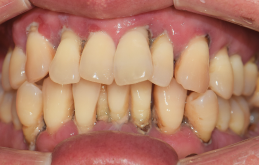

꼼꼼한 진료로 만족스러운 치료결과를 만들어드립니다.